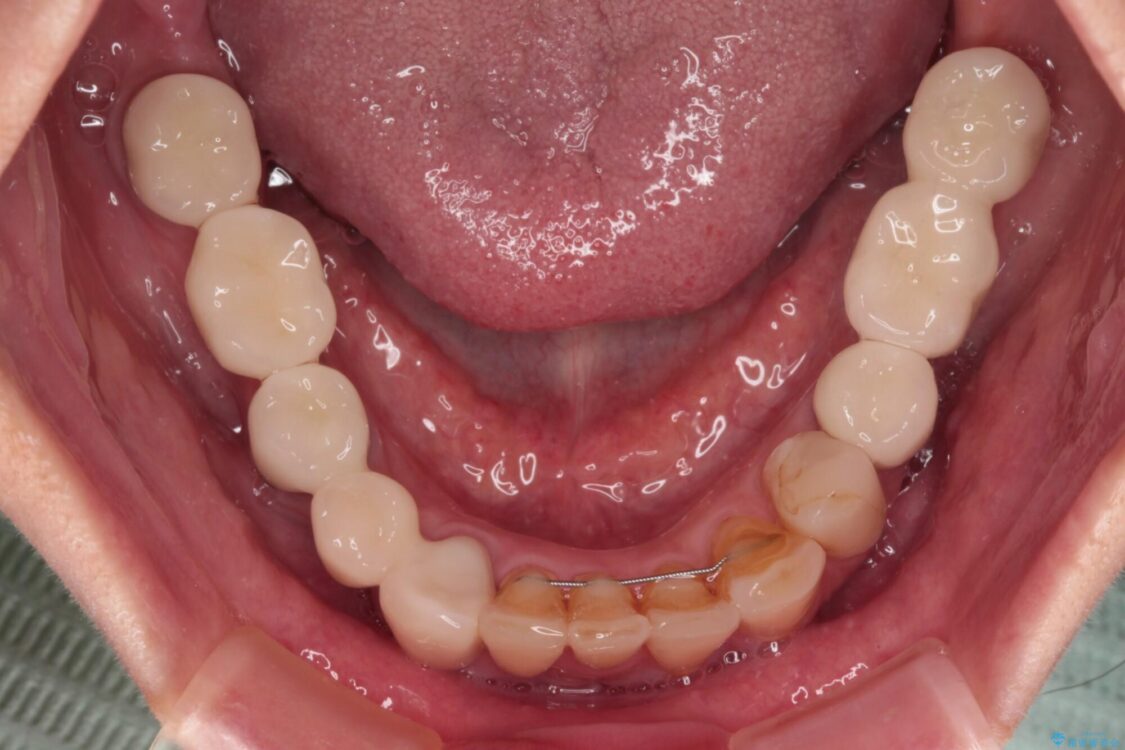

治療後

• 放置したインプラントとインビザライン 全顎リカバリー治療 治療後画像